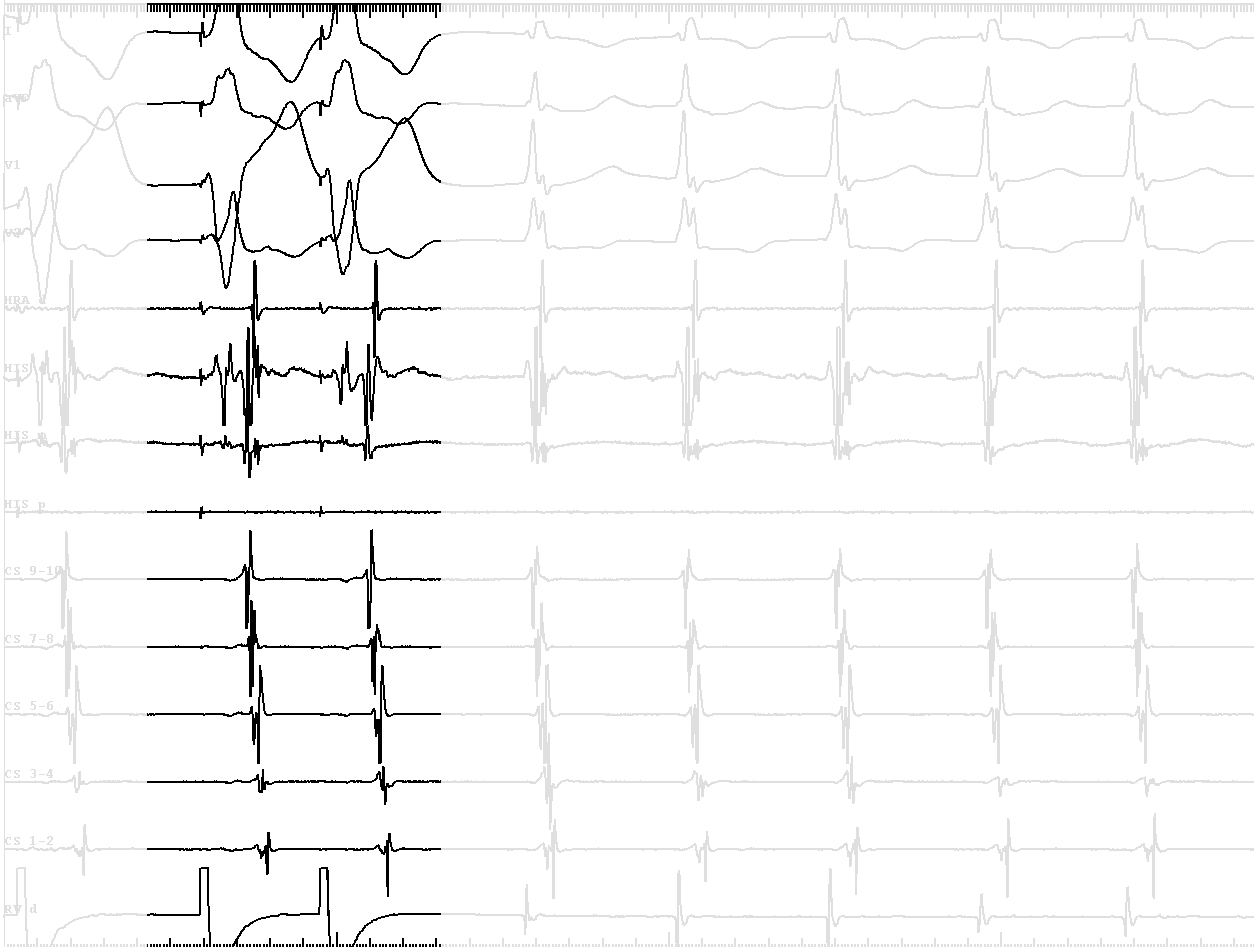

• VA conduction with His after A - ? AP

tachy_2.jpg

• VA conduction with His after A - bystander His activation, ? AP

• VH block with VA conduction - further confirms bystander His

tachy_3.jpg

• Short VA during tachycardia - not AVRT

• Narrow QRS similar to sinus - antegrade conduction through another AV node

tachy_4.jpg